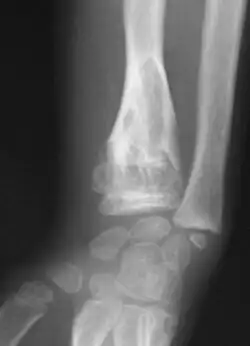

X-ray showing calcified enchondromas localized in finger a 37-year-old patient affected with Ollier disease -

Enchondromas localized in the upper part of the humerus of the same patient